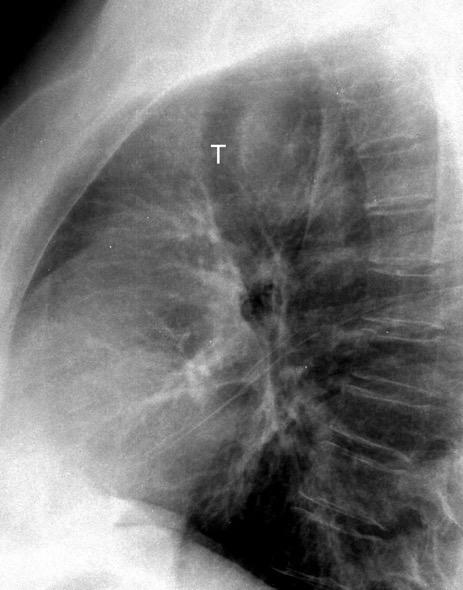

Raro. (2-9% de los T. tímicos). Asintomático. Contiene grasa (hasta 90%) y tejido timico (10-33%). Pueden ser muy grandes y confundirse con cardiomegalia. La tomografía “clásica” muestra los límites de la silueta cardiaca. (flechas)